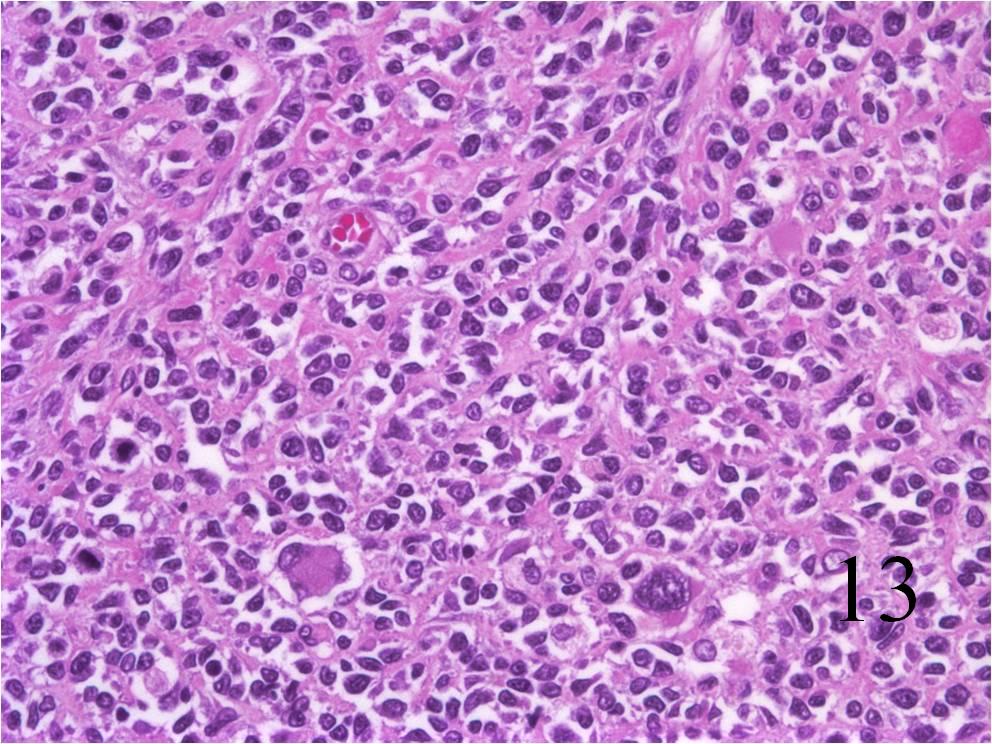

Microscopic

- Embryonal:

- Small round blue cells (Fig. 12-15)

- Round, oval, polygonal cells

- Fibrotic/myxoid stroma

- Rhabdomyoblast: well differentiated will have cross striations

- Alveolar:

- Tumor cells grow in nest or clusters

- Identify rhabdomyoblasts with cross striations